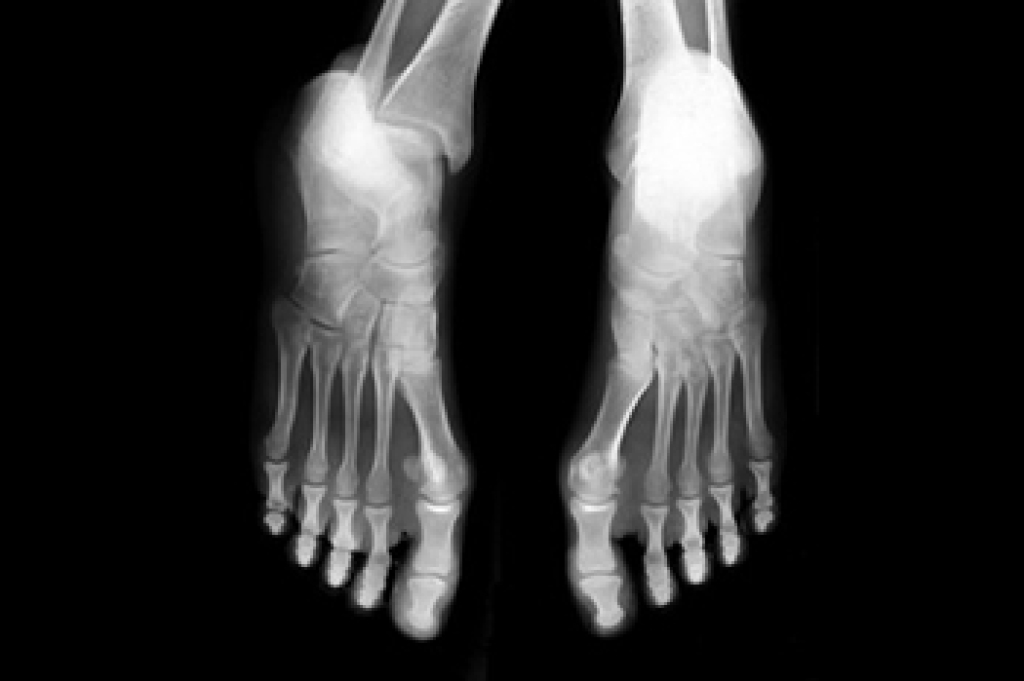

Achilles tendon injuries are diagnosed by a thorough physical evaluation, which can include an MRI. Treatment involves rest, physical therapy, and in some cases, surgery. However, various preventative measures can be taken to avoid these injuries, such as: